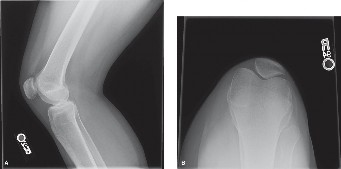

CASE 4 A 54-year-old skier injures his right knee on the last run of the day. …